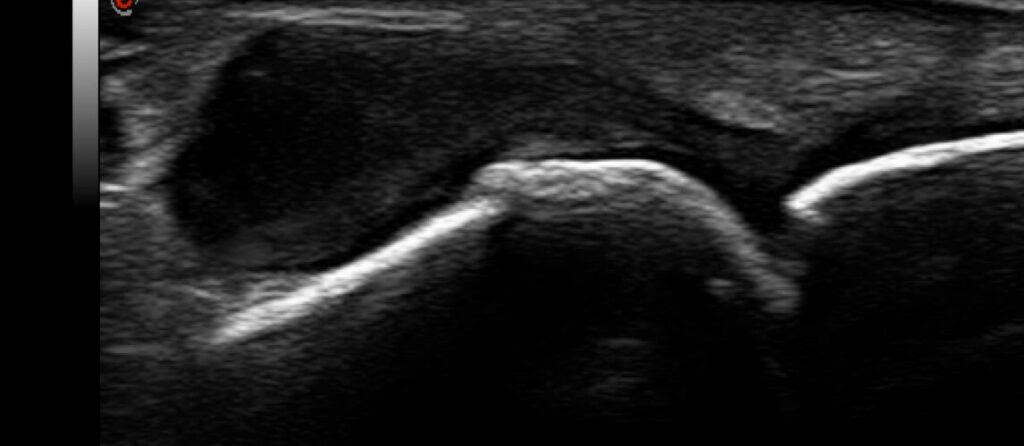

Comparison of power Doppler ultrasound and serum Vascular Endothelial Growth Factor (VEGF) in patients with rheumatoid arthritis under anti-inflammatory treatment.

Parysa Alborz a; Elena Neumann b; Ulf Müller-Ladner b; Johannes Strunk a;

a Krankenhaus Porz am Rhein, Abteilung für Rheumatologie, Urbacher Weg 19, 51149 Köln, Germany

b Kerckhoff Klinik, University of Giessen, Department of Rheumatology and Immunology, Beneckestr 2-8, 61231 Bad Nauheim, Germany